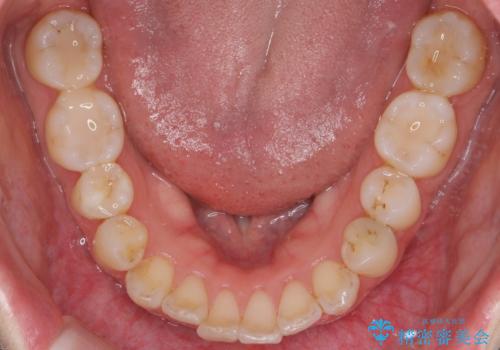

歯の着色を落としたい

- 表面の着色を気にされて、ご来院されました。

お話しをしたところ、リーズナブルに短時間で綺麗にしたいとの事でした。

そこでPMTCの30分コースで、目立つ部分を中心に落としていきました。

タバコのヤニ・茶渋などの歯の着色除去は、保険適用外になります。

当院ではブラシ・クリームで研磨するPMTCに加え、

細かい所まで着色除去できるエアフローも取り揃えておりますので、

落としたい範囲やご予算に応じて、ご相談に応じます。